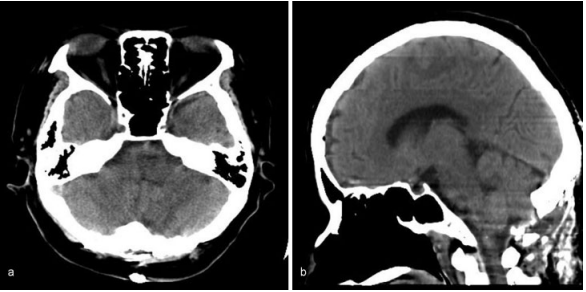

因此,她在入院后3天通过枕下中线入路以半坐位进行手术。枕下开颅术后,大脑池被打开收窄扁桃体和蚓部小舌。在右侧延髓观察到血肿,并通过冲洗清除血肿。血肿清除后,延髓肿胀减轻。术中神经生理监测(运动诱发电位和感觉诱发电位)保持不变。术中无海绵状畸形等病理学证据。术后CT显示血肿完全清除。手术后,她的自主呼吸提高到每分钟15次以上。术后5天停止呼吸机支持,术后6天拔管。术后5周核磁共振成像显示无结构异常。康复后,自主步行出院,没有进一步的并发症。

图:术后电脑断层扫描显示延髓血肿完全清除